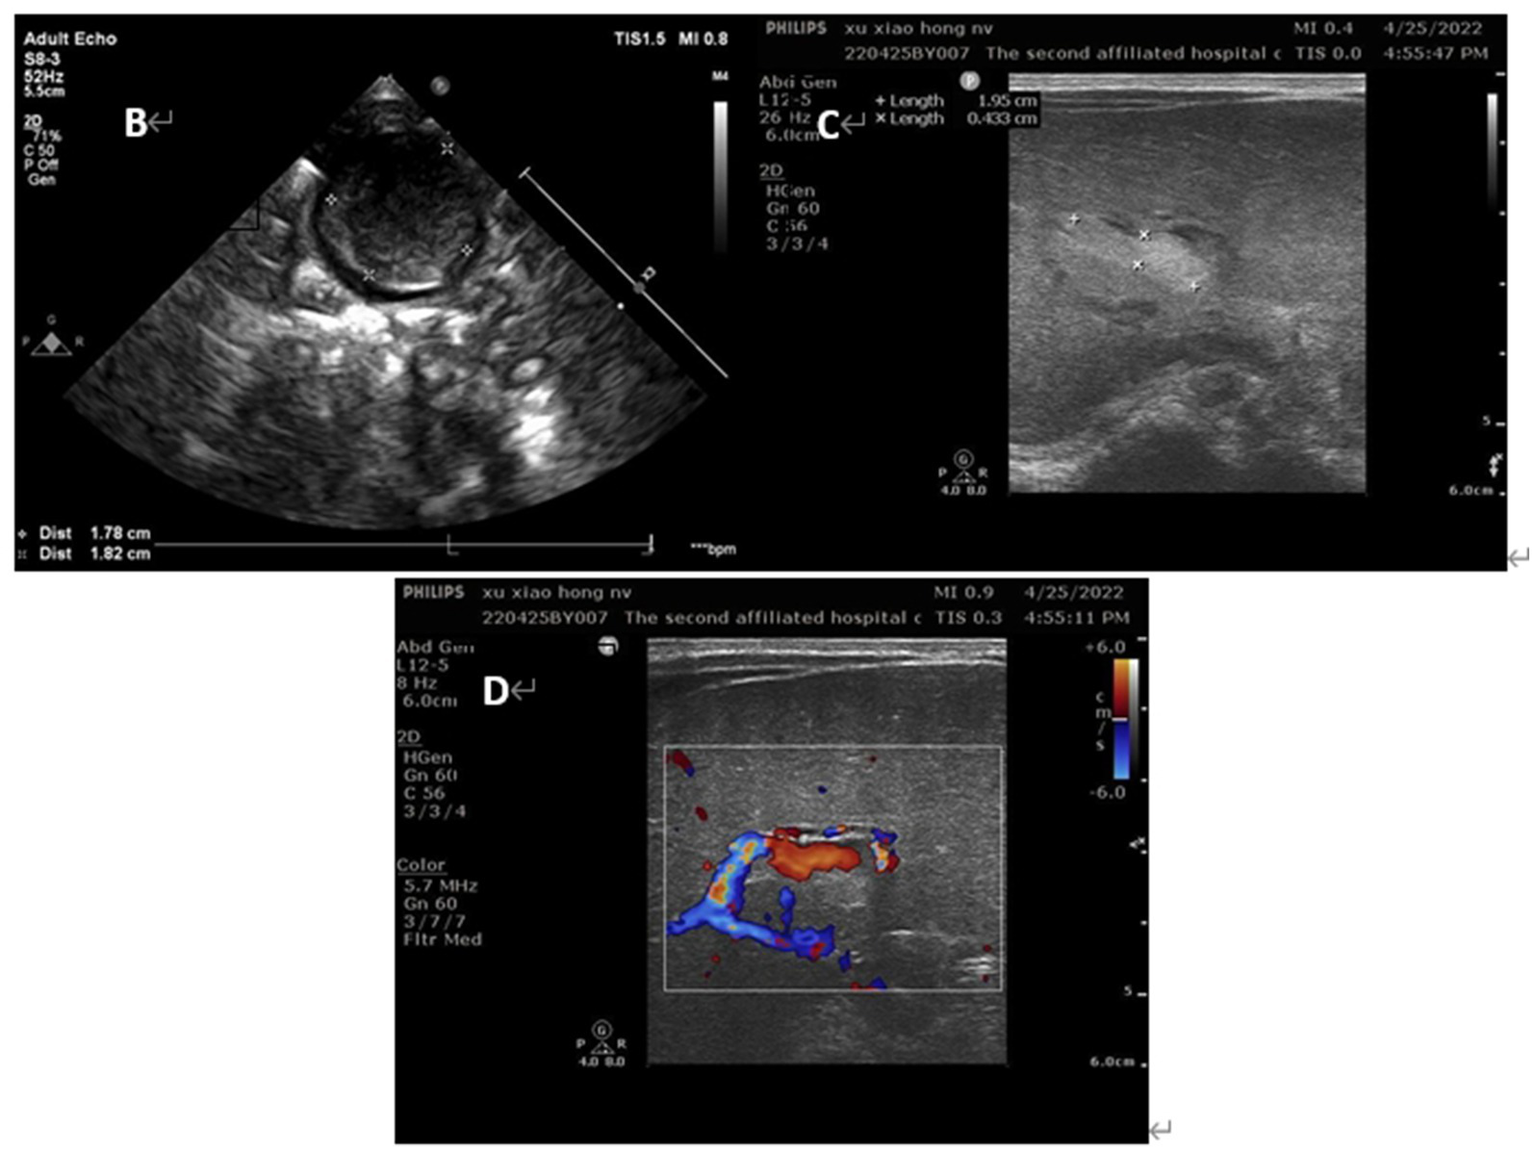

Her vital signs were normal, and her feeding was uneventful. On the second day of life, a second abdominal ultrasound confirmed the presence of a thrombus of 26 × 16 mm in umbilical vein thrombosis and a thrombus of 21 × 5 mm in portal vein (Figure 3). Fortunately, there was no thrombosis in the renal vein, splenic vein, superior mesenteric vein or inferior vena cava. Subsequent cerebral ultrasound excluded intracranial thrombosis. The laboratory examination made on admission found, white blood cells at 14.21× 109/L, hemoglobin at 175 g/L, platelets at 183× 109/L, and C-reactive protein (CRP) at 13.65 mg/L. Prothrombotic states were also evaluated: Protein C 26%, antithrombin III 48%, lupus ratio 0.58, d-dimer 2.38 μg/mL, and other indicators were within normal ranges.

Figure 3

Ultrasound images of the patients on day 2 of life (B) umbilical vein thrombus at day 2; (C) portal vein thrombus at day 2; (D) the blood flow signal decreased in the lumen of portal vein thrombosis at day 2.